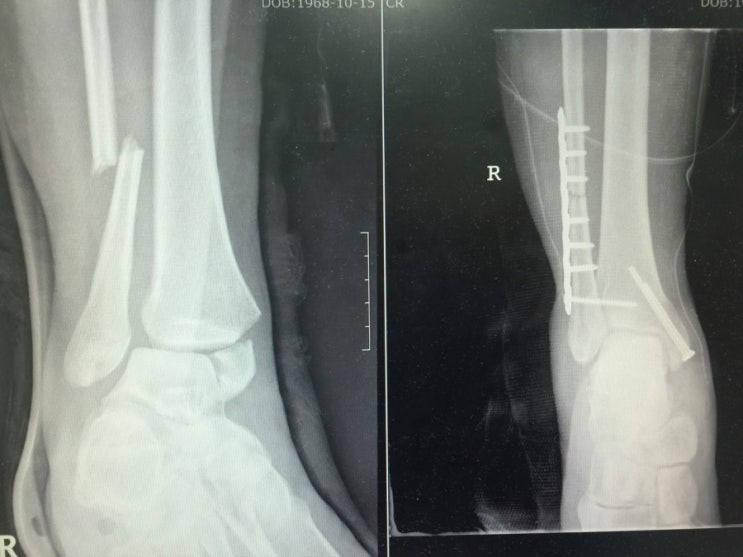

From www.alamy.com

Right Fibular Fracture and Fixation Stock Photo 7712199 Alamy What Is The Cpt Code For Orif Distal Fibula Fracture In c1 fractures, there is fracture of the fibula above the level of the syndesmosis. In this procedure, the provider treats a distal fracture of the fibula, or a break in the end of the fibula bone of the leg, including securing it. Open reduction and internal fixation (orif) is a type of surgery used to stabilize and heal a. What Is The Cpt Code For Orif Distal Fibula Fracture.